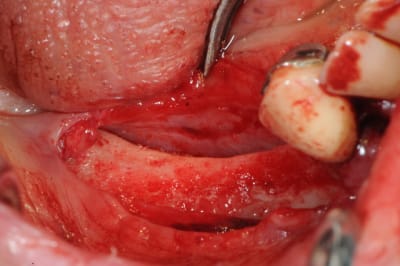

ou bien une comme ça:

--

xbk

"Si tous ceux qui croient avoir raison n'avaient pas tort, la vérité ne serait pas loin" Dac Pierre